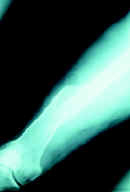

Caso clínico No 1. Paciente de 35 años, con fractura de la diáfisis femoral, manejado con clavo intramedular bloqueado y con consolidación a las 20 semanas.